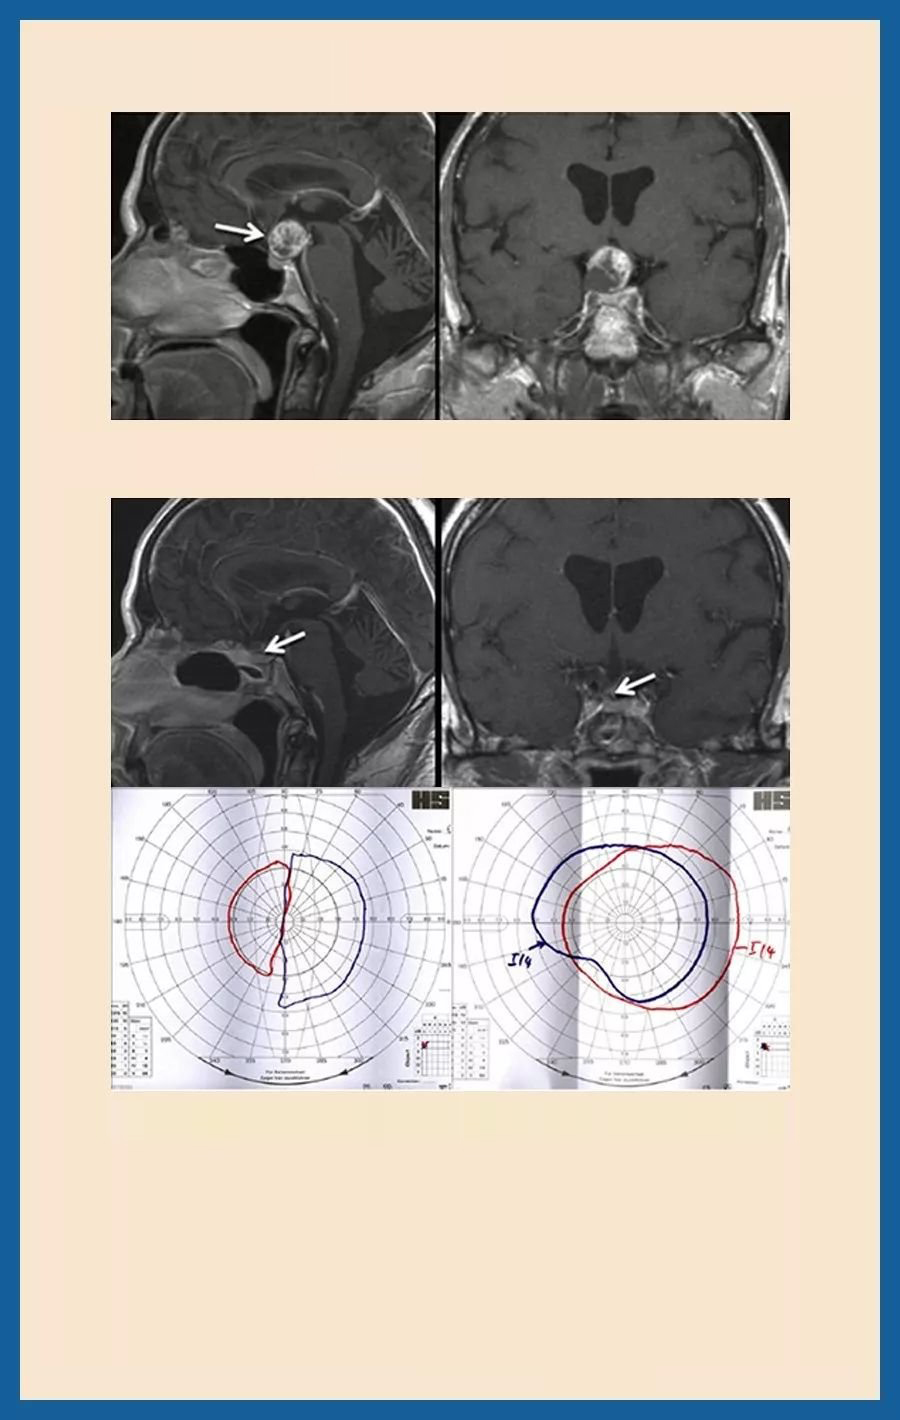

57岁,高度视力丧失、视野受限,颅咽管瘤。眼科检查显示左侧0.1和右侧0.2的视力以及高级双时间偏盲。

术前MRI:不对称的对比吸收性鞍上病变。

手术方法:神经内镜下颅咽管瘤微创切除术

术后情况:术后14天视野确定已经显示出外部边界的明显好转。视力右侧为1.0,左侧为0.9。短期尿崩症也已完全消退。术后一年MRI显示完全肿瘤切除,保留垂体姿势和脑下垂体。手术后2年,没有复发性肿瘤。